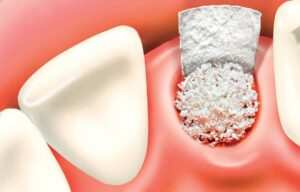

Після підняття мембрани отриманий простір між дном гайморової пазухи і мембраною заповнюється остеотропним матеріалом.

Імплантат впроваджується в це, вже підготовлене ложе після введення матеріалу.

За допомогою спеціального шприца остеотропний матеріал вводиться в утворений простір між дном гайморової пазухи і мембраною Шнайдера.

Під час заповнення новоствореної порожнини кістковозаміщуючим матеріалом особливу увагу лікар хірург приділяє недопущенню утворення пустот і забезпечення щільного співставлення матеріалу зі стінками кістки.